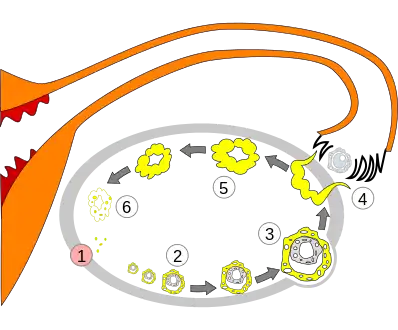

Order of changes in ovary

Order of changes in ovary Human ovary with fully developed corpus luteum